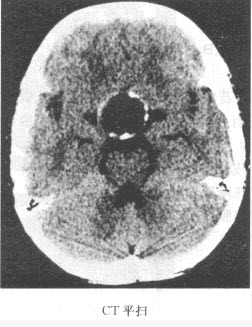

F.CT示脑实质内低密度区不强化

2、单项选择题 患者,女,80岁,被人发现昏迷,大小便失禁10小时入院。体格检查:血压180/100mmHg,心率约110次/分,有房颤,体温37℃,浅昏迷,右侧肢体未见自主活动,肌力增高,Babinski征阳性,GCS=E2+V1+M3=6分,有风湿性心脏病和房颤病史,既往超声检查有二尖瓣赘生物。

患者检查图像如下,你考虑何种疾病()

A.脑出血

B.脑梗死

C.脑动静脉畸形

D.脑膜炎

E.星形细胞瘤

F.脑膜瘤压迫静脉窦